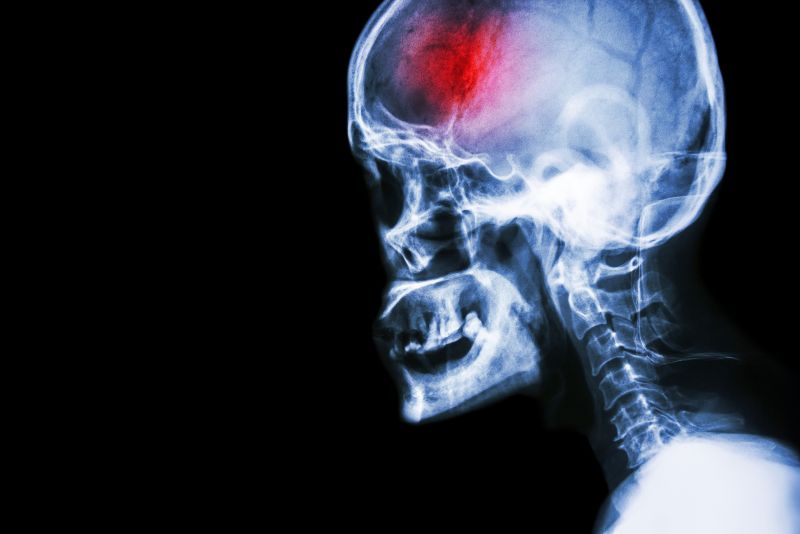

What is a stroke?

A stroke (previously known as a cerebrovascular accident) when there is a decreased flow of blood to the brain from either a blockage in the blood vessels that supply the brain (ischemic stroke), or a bleed from the blood vessels that supply the brain (hemorrhagic stroke). When the blood flow to the brain is blocked it prevents the brain from getting the needed oxygen and nutrients to function. Without oxygen the brain cells can be permanently damaged or die and the physical and mental functions related to that area of the brain will be affected. A stroke is a medical emergency and rapid treatment is crucial to decreasing the damage caused by a stroke.